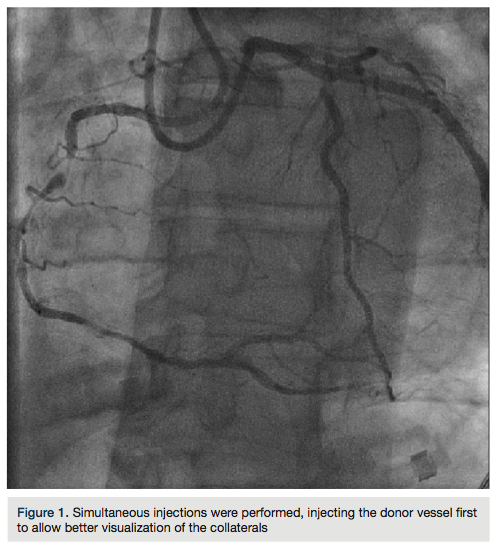

Dual access was obtained with 6 French (Fr) Glidesheaths (Terumo) in both radial arteries and

then upsized to 7 Fr sheaths, followed by administration of the radial cocktail (2500 units of heparin, 2.5 mg). From the left radial, we used an Amplatz left (AL)1 catheter with side holes to engage the RCA. From the right radial, an Extra Back-Up (EBU) 3.5 guide catheter was used to engage the left system. Simultaneous injections were performed, injecting the donor vessel first to allow better visualization of the collaterals (Figure 1). The initial strategy was to attempt antegrade crossing first and switch to a retrograde approach if unsuccessful. We then administered heparin to an activated clotting time (ACT) >250. A Fielder XT wire (Abbott Vascular) and an over-the-wire 1.5 x 8mm Emerge balloon (Boston Scientific) were used to wire the RCA and it was felt we entered the subintimal space. We left this wire in the false lumen and

Radial access is an alternative access for CTOs with equivalent success rates compared to femoral access in experienced operators. Dual injection is recommended for adequate visualization of the CTO length, as well as visualization of the collaterals (septals or epicardials) for the retrograde approach. When adopting the hybrid algorithm, it is probably better to start with femoral access and large-caliber guides until one is comfortable with this approach and its variations. After overcoming the learning curve for both radial and CTOs, is then reasonable to transition to a radial approach. For more information about CTOs and the hybrid algorithm, visit https://www.ctofundamentals.org.